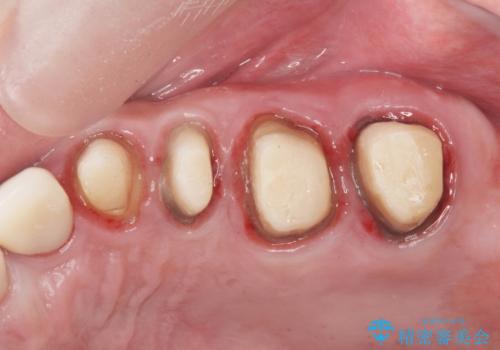

ここの歯の状態を精密に検査し、根管治療、セラミック治療、インプラント治療を含む総合的な歯科治療を計画します。

- 242万円(ジルコニアクラウン・仮歯×7本 インプラント×2本)費用は治療当時の料金となります